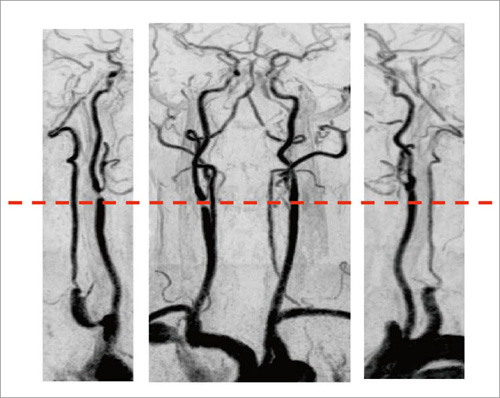

頸部造影3D MRA

頸部造影3D MRAの撮像法を表1-(4)に,画像を図6に示す。まず,2D RSSGによるMR透視で,造影剤の到達状況を確認しながら3D MRAを撮像する。これは,日立メディコ社の“FLUTE”という撮像法である。図6 aはMR透視のオリジナル画像,図6 bはリアルタイムに処理されたサブトラクション画像である。検査時にはこの2つの画像が表示されているが,誰が見てもわかりやすいという点では,サブトラクション画像は非常に優れている。

この後にフィルム出力処理を行うが,ECHELON Vegaで特徴的なのは,フィルムのフォーマットが自由に決められるということである(図6 c,d)。そのため,臨床医が見やすい画像を提供することができる。

図6 頸部造影3D MRA(FLUTE)